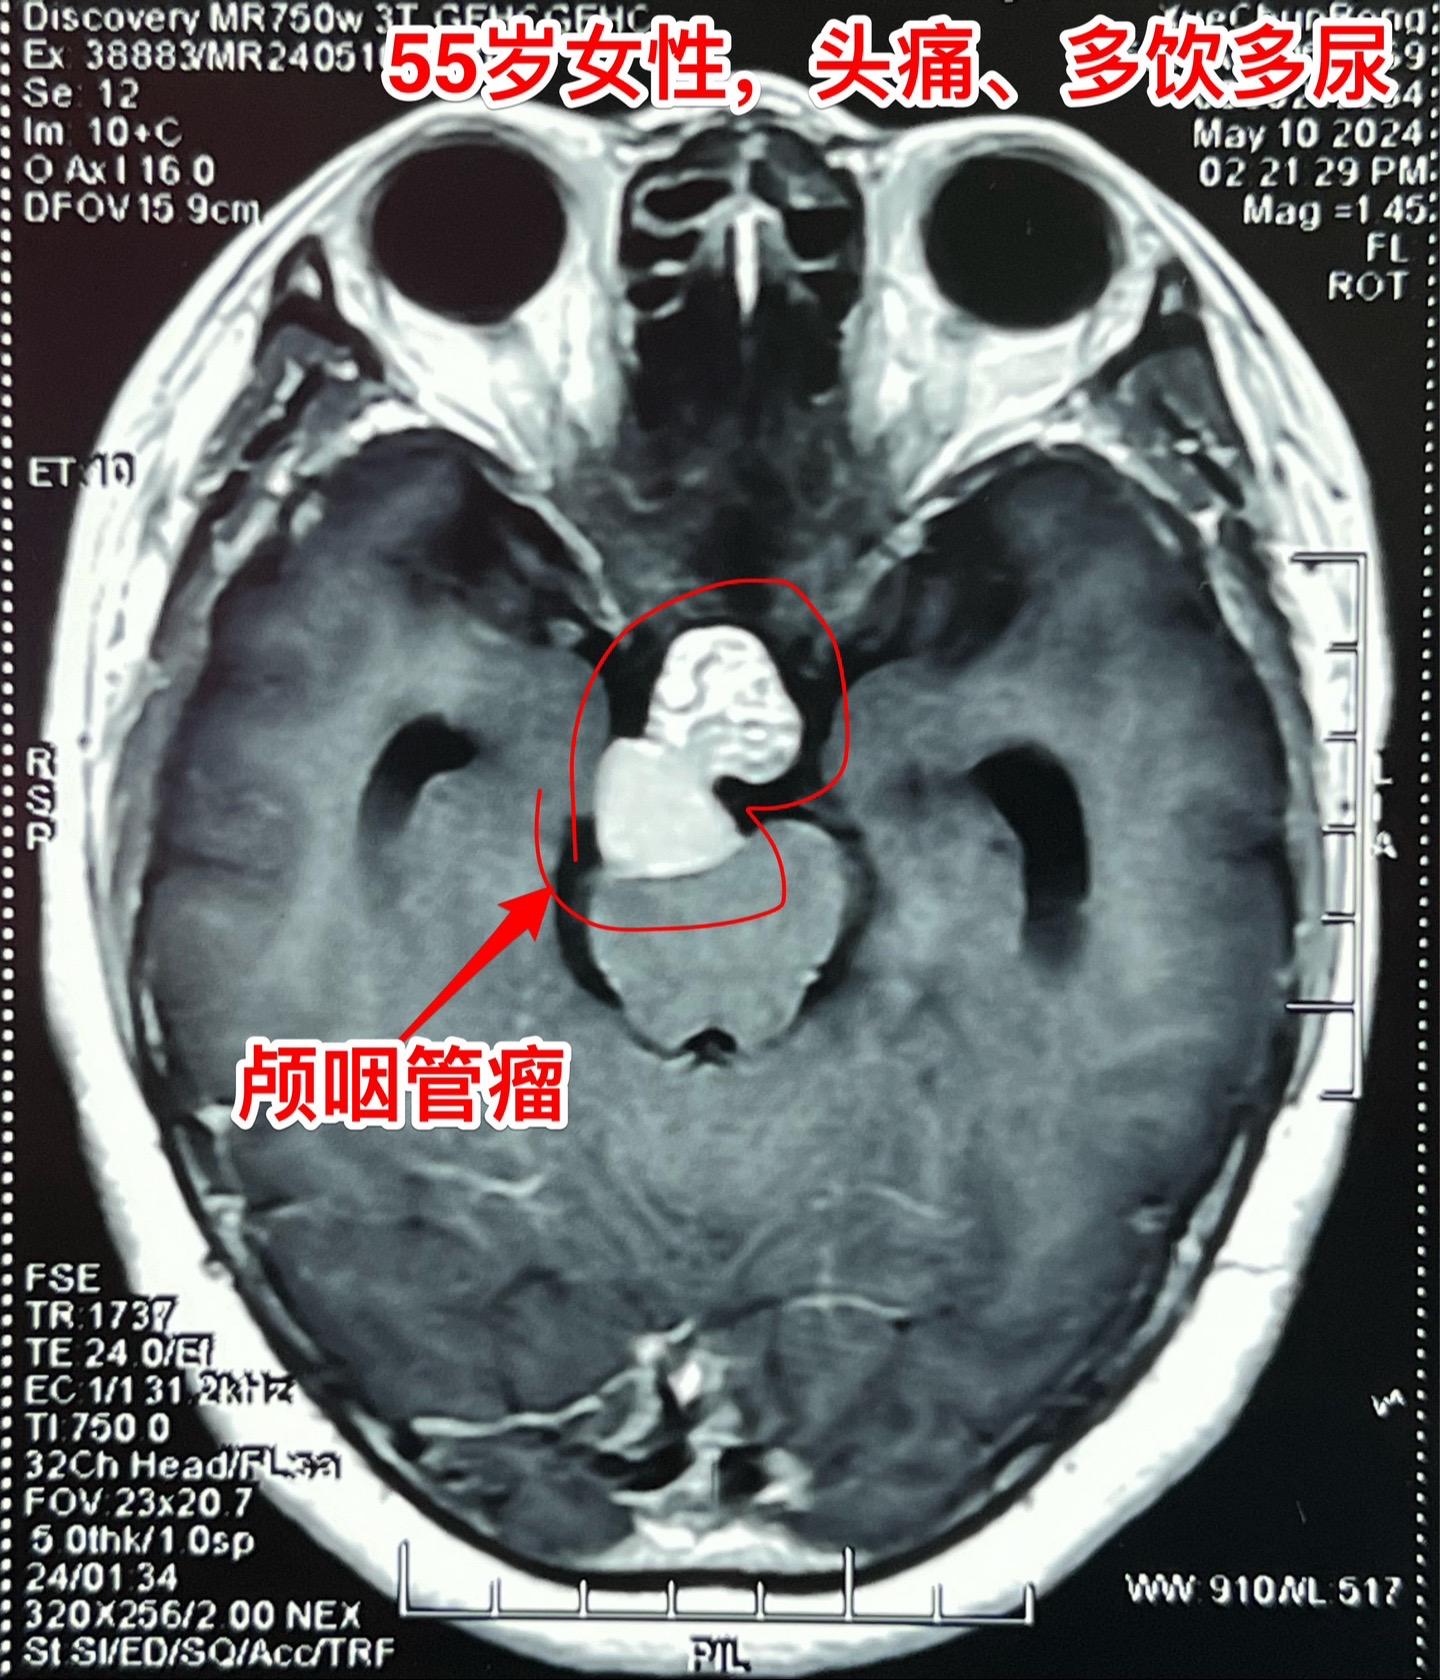

5月16日两个颅咽管瘤手术。五一假期后开展的手术都是颅咽管瘤切除手术。经常一天作两个颅咽管瘤手术!这样的劳动强度有点大! 5.16一天两个颅咽管瘤手术,肿瘤有相似的特征,两个都有大块的钙化斑;都是从垂体柄侵入垂体中;手术方式也相似-经额底纵裂入路。 手术后两个病人都顺利从ICU转移到普通病房。

5月16日两个颅咽管瘤手术。五一假期后开展的手术都是颅咽管瘤切除手术。经常一天作两个颅咽管瘤手术!这样的劳动强度有点大! 5.16一天两个颅咽管瘤手术,肿瘤有相似的特征,两个都有大块的钙化斑;都是从垂体柄侵入垂体中;手术方式也相似-经额底纵裂入路。 手术后两个病人都顺利从ICU转移到普通病房。颅咽管瘤